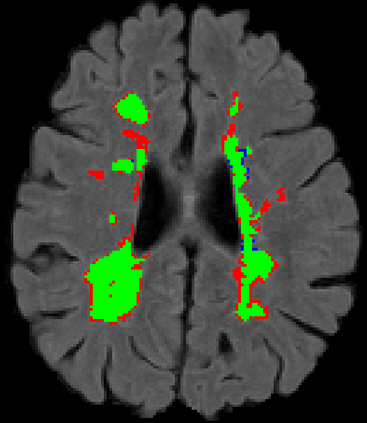

Recently, segmentation methods based on Convolutional Neural Networks (CNNs) showed promising performance in automatic Multiple Sclerosis (MS) lesions segmentation. These techniques have even outperformed human experts in controlled evaluation conditions such as Longitudinal MS Lesion Segmentation Challenge (ISBI Challenge). However state-of-the-art approaches trained to perform well on highly-controlled datasets fail to generalize on clinical data from unseen datasets. Instead of proposing another improvement of the segmentation accuracy, we propose a novel method robust to domain shift and performing well on unseen datasets, called DeepLesionBrain (DLB). This generalization property results from three main contributions. First, DLB is based on a large group of compact 3D CNNs. This spatially distributed strategy ensures a robust prediction despite the risk of generalization failure of some individual networks. Second, DLB includes a new image quality data augmentation to reduce dependency to training data specificity (e.g., acquisition protocol). Finally, to learn a more generalizable representation of MS lesions, we propose a hierarchical specialization learning (HSL). HSL is performed by pre-training a generic network over the whole brain, before using its weights as initialization to locally specialized networks. By this end, DLB learns both generic features extracted at global image level and specific features extracted at local image level. DLB generalization was validated in cross-dataset experiments on MSSEG'16, ISBI challenge, and in-house datasets. During experiments, DLB showed higher segmentation accuracy, better segmentation consistency and greater generalization performance compared to state-of-the-art methods. Therefore, DLB offers a robust framework well-suited for clinical practice.